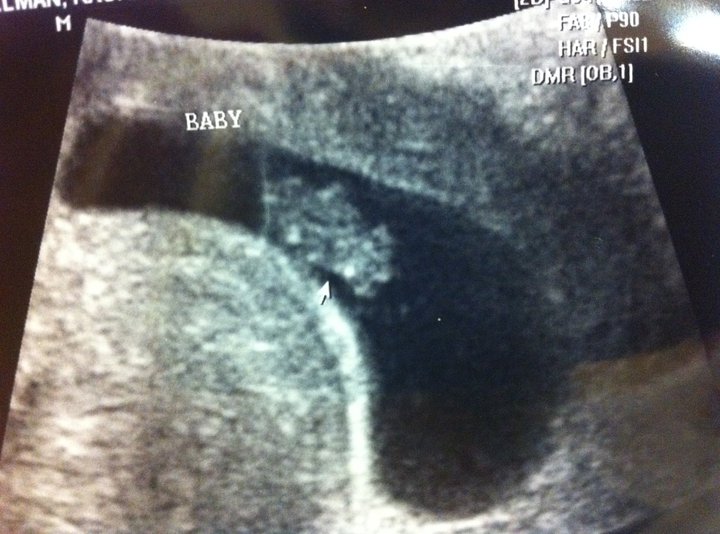

We saw our little peanut today. I've never had an ultrasound this early!! There he/she is!! In all his/her fetal glory!!

I am eight weeks.

I am due in July.